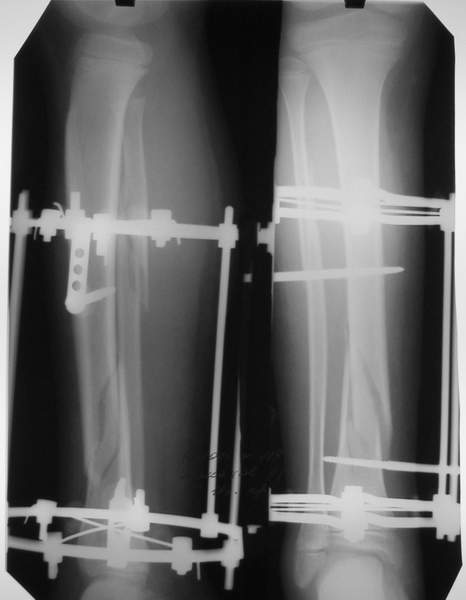

В аттачтах №№ 1 и 2 - примеры, когда 2 кольца не позволили послеоперационно

исправить смещение фрагментов большеберцовой (по ширине и вальгусное).

А казалось бы (#2) - поиграй на штангах и все влетит.

Оперировал не я

В аттачте № 3 - один из примеров полукольцевого аппарат...

Это уже я баловался.

Итог? Работы больше (по времени и

интраоп "подгонке"), срастается также, а особого преимущества по сравнению с

"чиста" кольцевым (вес, удобство ношения и пр.) - я, по крайней мере,

не нашел.

Теперь не балуюсь.